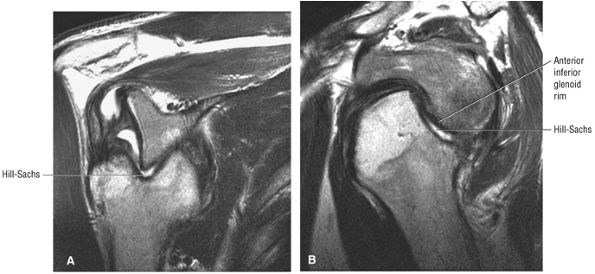

MR arthrography optimizes depiction of biceps pulley lesions, with improved appreciation of the degree of injury to the CHL and SGHL.

-

Non-contrast studies are satisfactory for characterization of gross subluxation of the biceps.